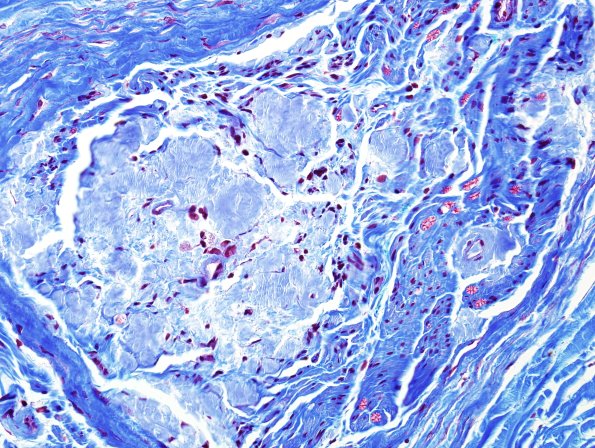

Washington University Experience | PERIPHERAL NEUROPATHY | 14 AMYLOID NEUROPATHY | 2B2 Amyloid Neuropathy (Case 2) Trichrome 4

This trichrome stain again demonstrates differences between endoneurial collagen and amyloid. In some cases the separation of a mixture of collagen and amyloid may complicate the recognition of both. (Trichrome)